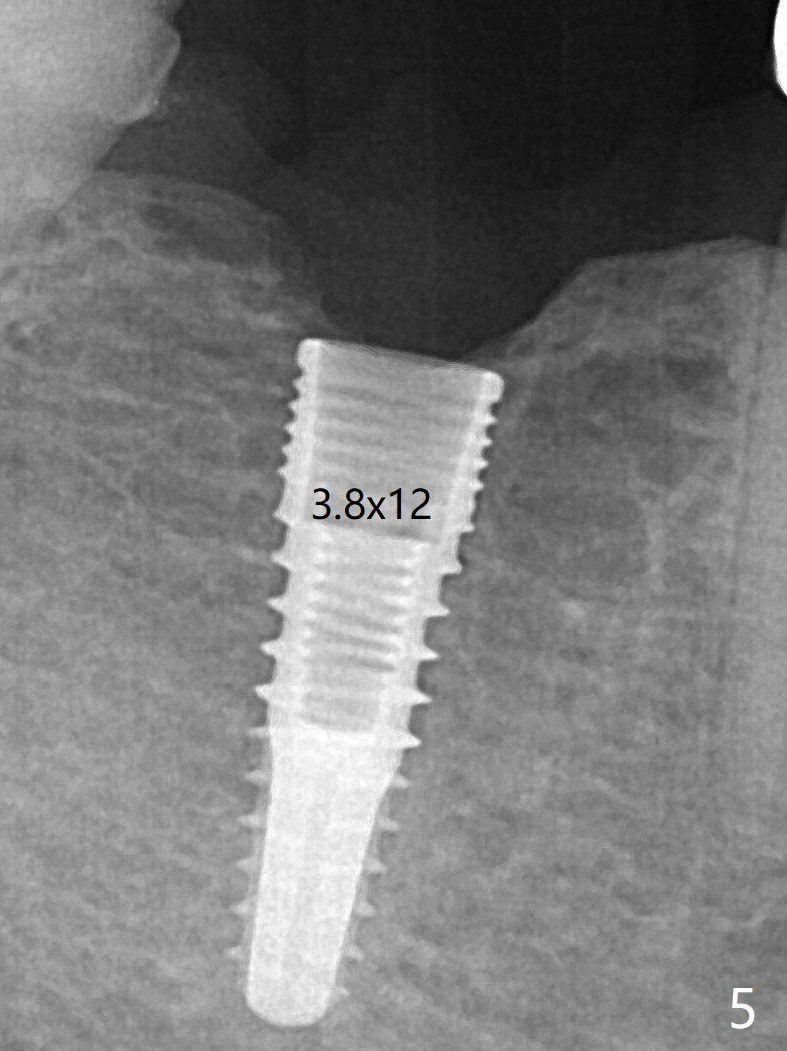

When a 3.8x12 mm SM implant is placed with 40 Ncm, there is 1-2 mm cortical bone buccolingually (primary stability, Fig.4,5). The thick cortices do not seem to be easy to be bent, i.e., expanded. There appears dense bone formation 3 months postop (Fig.8 *). One year post cementation, the crown at #31 needs recementation (Fig.9); the bone density next to the coronal implant increases (*).